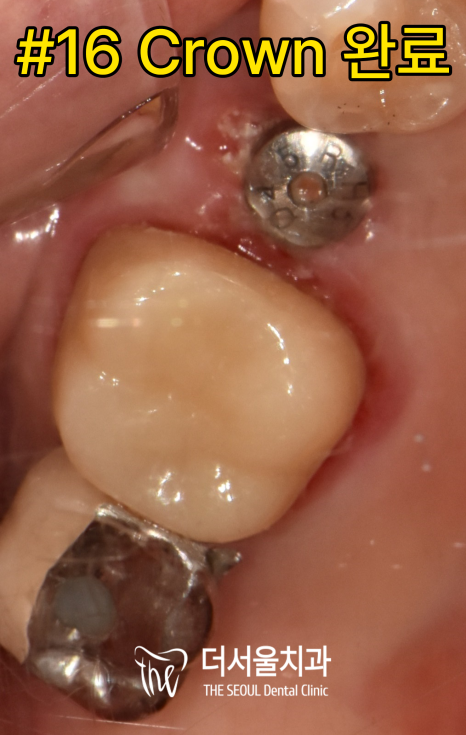

이어서 러버댐(Rubber dam)을 사용하여

대구치 근관수복을 완료했습니다.

삭제(Prep)을 최소화 한 후

크라운을 올려드려 수복을 마무리했습니다.

단단하게 잘 고정된 픽스처에

크라운까지 장착 후